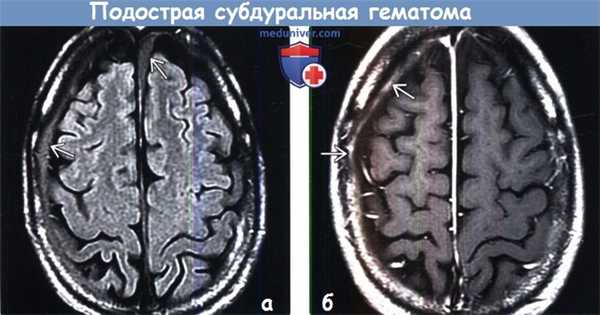

• Подострая субдуральная гематома (пСДГ)

• Подострое (приблизительно от трех дней до трех недель) скопление частично лизированного тромба и резорбирующихся продуктов крови, окруженное грануляционной тканью («мембраной»)1. Общие характеристики подострой субдуральной гематомы:

• Лучший диагностический критерий:

о Внемозговая гематома в форме полумесяца КТ-плотностью от изо- до гиподенсной, распространяющаяся диффузно над полушариями

о КТ-плотность и интенсивность сигнала на МР-томограммах меняются в зависимости от давности кровоизлияния и наличия организации![Подострая субдуральная гематома на КТ]()

• Бесконтрастная КТ:

о КТ-плотность от изо- до гипоинтенсивной; может иметь такую же плотность, как нижележащая кора головного мозга

о Медиальное смещение перехода между серым и белым веществом (СВ БВ)

о Поверхностные борозды не доходят до внутренней пластинки костей свода черепа

о Возможна визуализация линии «точек» из спинномозговой жидкости (СМЖ), сформированных за счет смещенных/компримированных борозд

о Плотность варьирует в зависимости от стадии эволюции гематомы:

- Последовательное развитие КТ-плотности гематомы от гиперденсной (острая СДГ) через изоденсную (пСДГ) до гиподенсной (хроническая СДГ) в течение - 3 недель

- Повторное кровоизлияние может обусловливать смешанную плотность гематомы

(б) MPT, Т1 -ВИ: у этого же пациента определяется билатеральное субдуральное скопление жидкости, слегка гиперинтенсивное по отношению к СМЖ. Такая МР картина типична для подострой СДГ4. Рекомендации по визуализации:

(а) MPT, FLAIR: у этого же пациента выявляется отсутствие подавления сигнала от подострых скоплений жидкости, что отражает их отличие от нормальной СМЖ.

(б) МРТ, постконтрастное Т1 -ВИ: у этого же пациента определяется, что наружная мембрана пСДГ накапливает контраст. Указанные признаки характерны для гематомы в поздней подострой стадии.в) Дифференциальная диагностика подострой субдуральной гематомы: